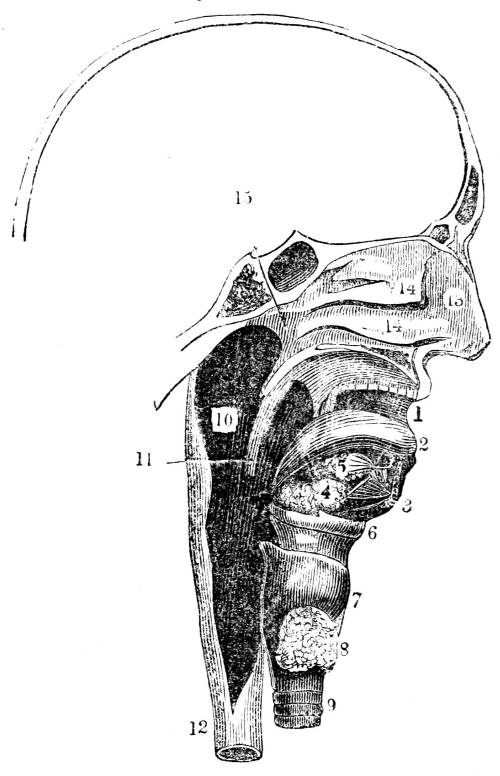

Fig. CXXXV.—

View of the Air Tubes and Lung.

1. The larynx. 2. Trachea. 3. Right bronchus. 4.

Left bronchus. 5. Left lung; the fissures denoted by the

two lines which meet at 6, dividing it into three lobes,

and the smaller lines on its surface marking the division of

the lobes into lobules. 7. Large bronchial tubes. 8. Minute

bronchial tubes terminating in the air cells or vesicles.

359. The apparatus consists of a vessel to carry

the air to the blood; a vessel to carry the blood

to the air; an organ in which the air and the

blood meet; and an organization by which both

fluids are put in motion. The vessel that carries

the air to the blood is the windpipe (fig. CXXXV.39

1, 2); the vessel that carries the blood to the air

is the pulmonary artery (fig. CXL. 7); the organ

in which the blood and the air meet is the lung

(fig. CXXXV. 5); the organization which puts the

air in motion, is the structure of bones, cartilage

and muscles, called the thorax (figs. CXLI. and

CXLVI. ), and the engine that communicates motion

to the blood is the right ventricle of the heart

(fig. CXL. 5).

360. The windpipe is a tube which extends

from the mouth and nostrils to the lung (figs.

CLIII. 1, 9, and CXXXV. 2, 5). It is attached to

the back part of the tongue (fig. CLII. 2, 9),

and passes down the neck immediately before

the esophagus, or the tube which leads to the

stomach (fig. CLIII. 9, 12).